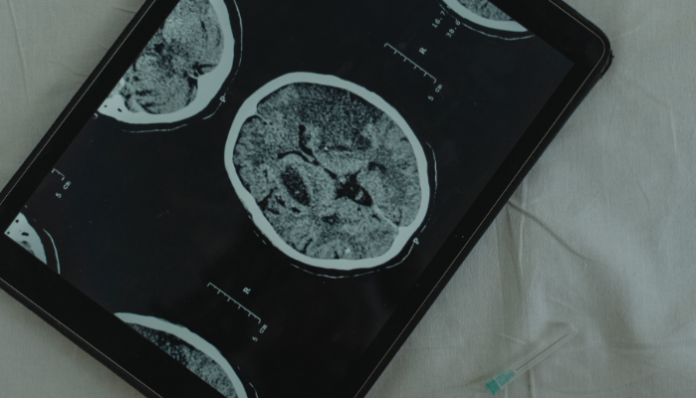

“Las metástasis encefálicas son la complicación neurológica más frecuente en los pacientes oncológicos. La radioterapia ha jugado un papel angular en el tratamiento de estos pacientes y los resultados han sido cada vez mejores, no solo en cuanto a las respuestas al tratamiento sino a una reducción cada vez mayor de los efectos secundarios”. Así resume su artículo para la revista Tendencias en Medicina Alejandro Santini Blasco, jefe de la Unidad de Radioterapia del Centro Oncológico del Norte, Antofagasta, Chile, titulado “Tratamiento de las metástasis encefálicas – un tema cada vez más complejo –”.

En su texto, Santini analiza los últimos avances y el manejo actual de los pacientes con metástasis encefálicas.